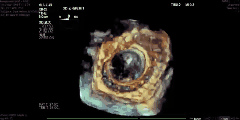

据了解,当天一共完成了4例介入二尖瓣置换产品动物实验,由泰州美凤力动物实验中心创始人、首席科学家魏旭峰亲率团队在活体白猪身上经心尖介入完成二尖瓣置换,手术过程非常顺利,从心尖介入到最后瓣膜释放,仅仅用时两分钟。术后,通过超声对瓣膜功能进行了评价,没有明显瓣周漏,瓣膜活动状态良好,跨瓣压差小,没有瓣膜反流,也没有阻挡左室流出道。又通过直接测压的手段进行了左房压测定,亦无明显升高。术后效果得到了手术团队的高度认可与赞扬。

-术后造影-